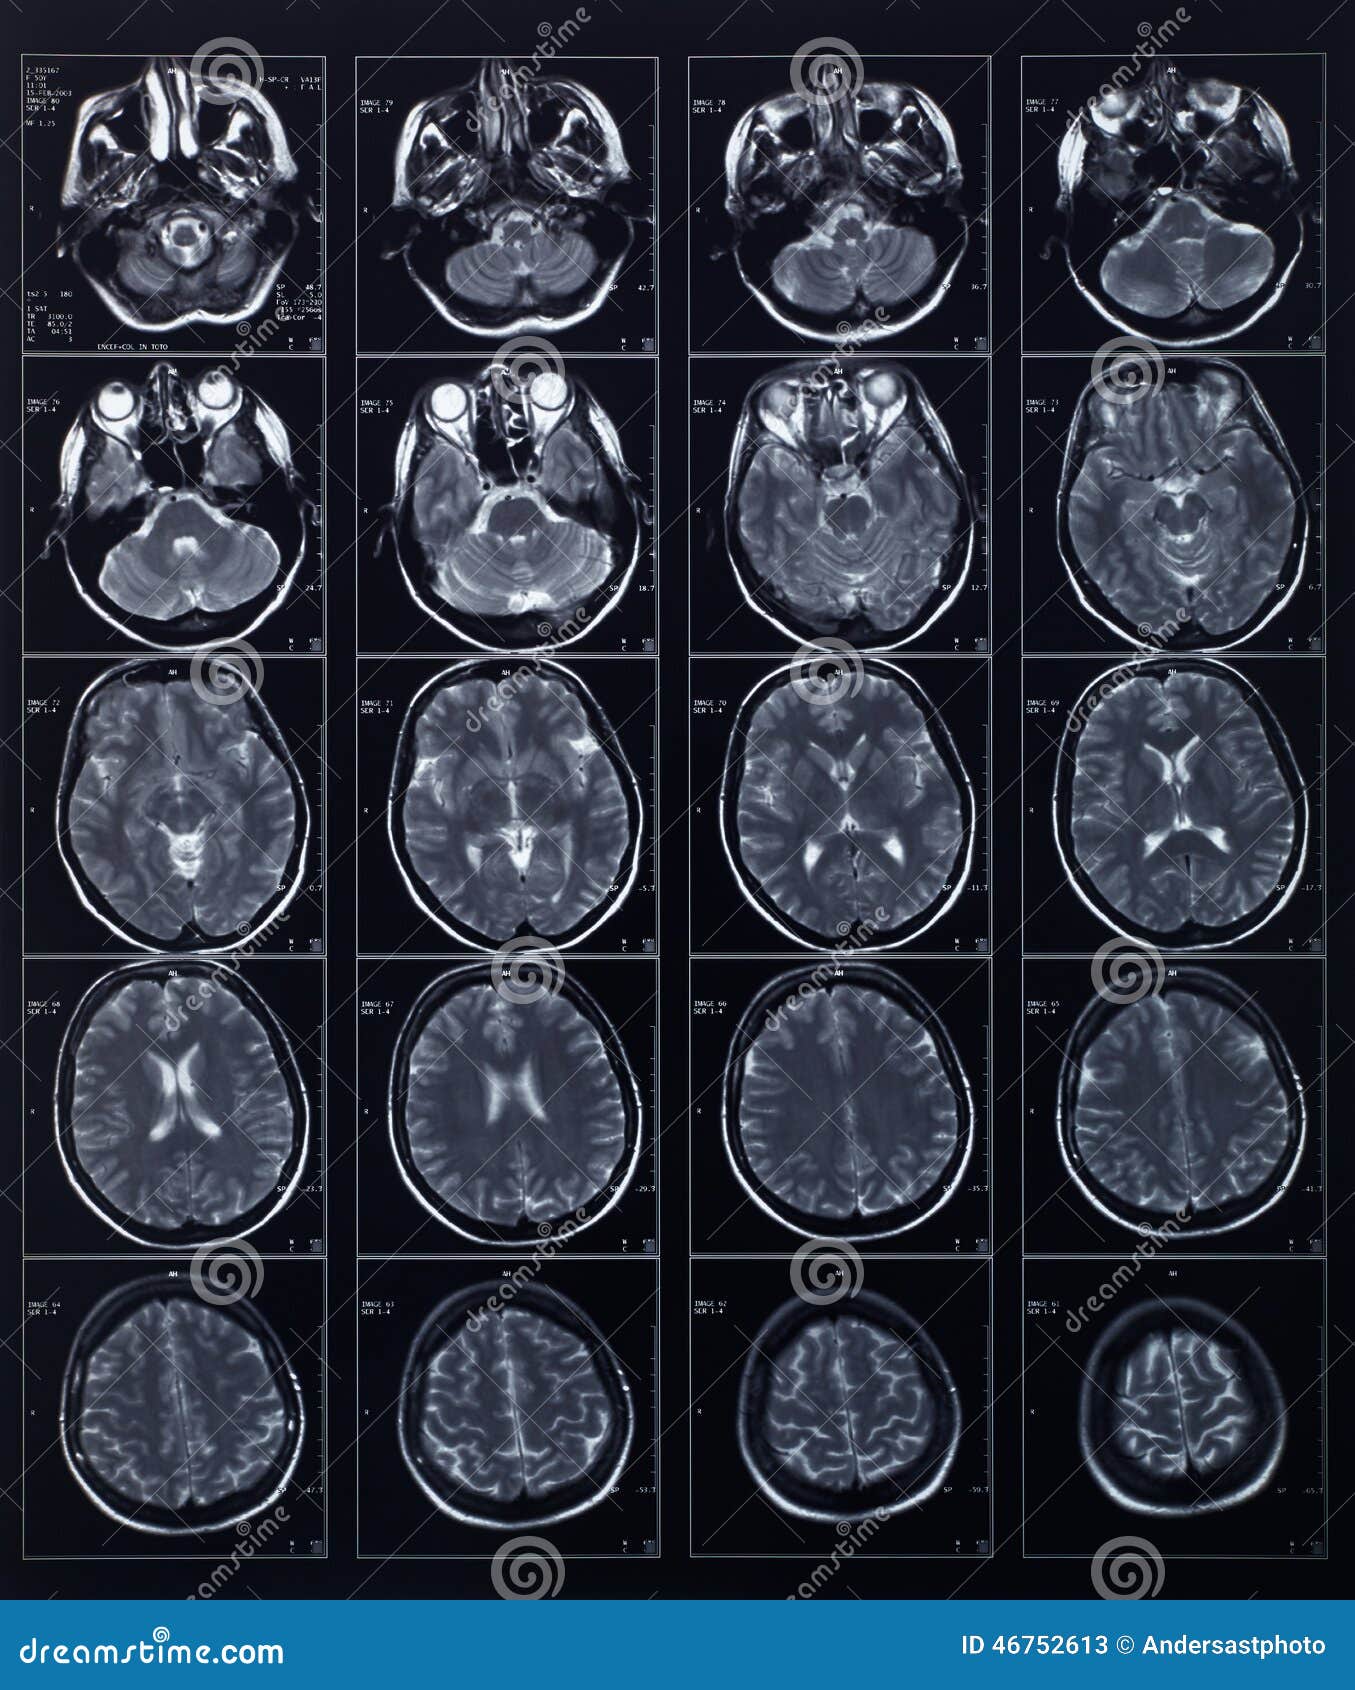

L Imaging Dell Encefalo Tc Ed Rm A Confronto

Risonanza Magnetica Encefalo Medical Imaging Caserta

Tecniche Di Diagnostica Per Immagini In Neurologia

Risonanza Magnetica Encefalo A Cosa Serve Radiologia Italia

Atlante Di Resonanza Magnetica Del Cervello